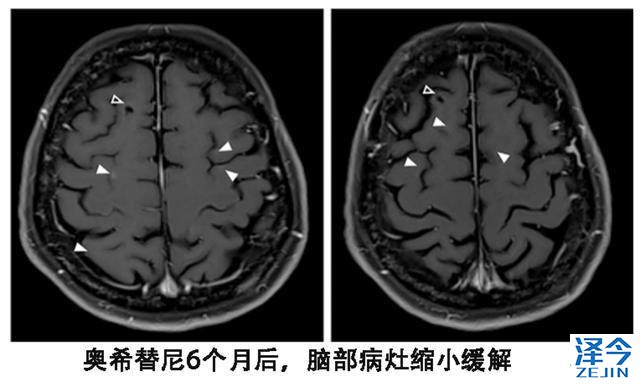

患者尽管血液基因检测T790M阴性,但是依然换用了第三代靶向药物泰瑞沙(AZD9291),每天的剂量为80毫克,结果出现了奇迹。患者的视觉双影没有了,脑脊液的细胞学检查也为阴性,脑部核磁显示脑皮质损伤有所改善。

尽管血液T790M检测为阴性,从换用9291之后,患者脑部病灶稳定了一年,另外脑外的病灶一直处于稳定状态。